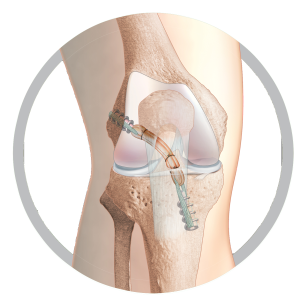

Short Graft ACL

The original short-graft ACL reconstruction technique

Unique to the TLS system is its hand reamed retrograde tunnels which gives the possibility to fine-tune tunnel position per-operatively. As a result, studies have shown the TLS to produce less post-operative pain than traditional techniques and other short graft procedures² whilst also producing excellent long-term patient outcomes.

Re-rupture rates are reported at anywhere between 1.9%³ and 6% at 2 years in various independent peer reviewed papers.⁴ In addition, graft preparation is simple and versatile, allowing the surgeon to adjust graft size slightly to match the patient anatomy.